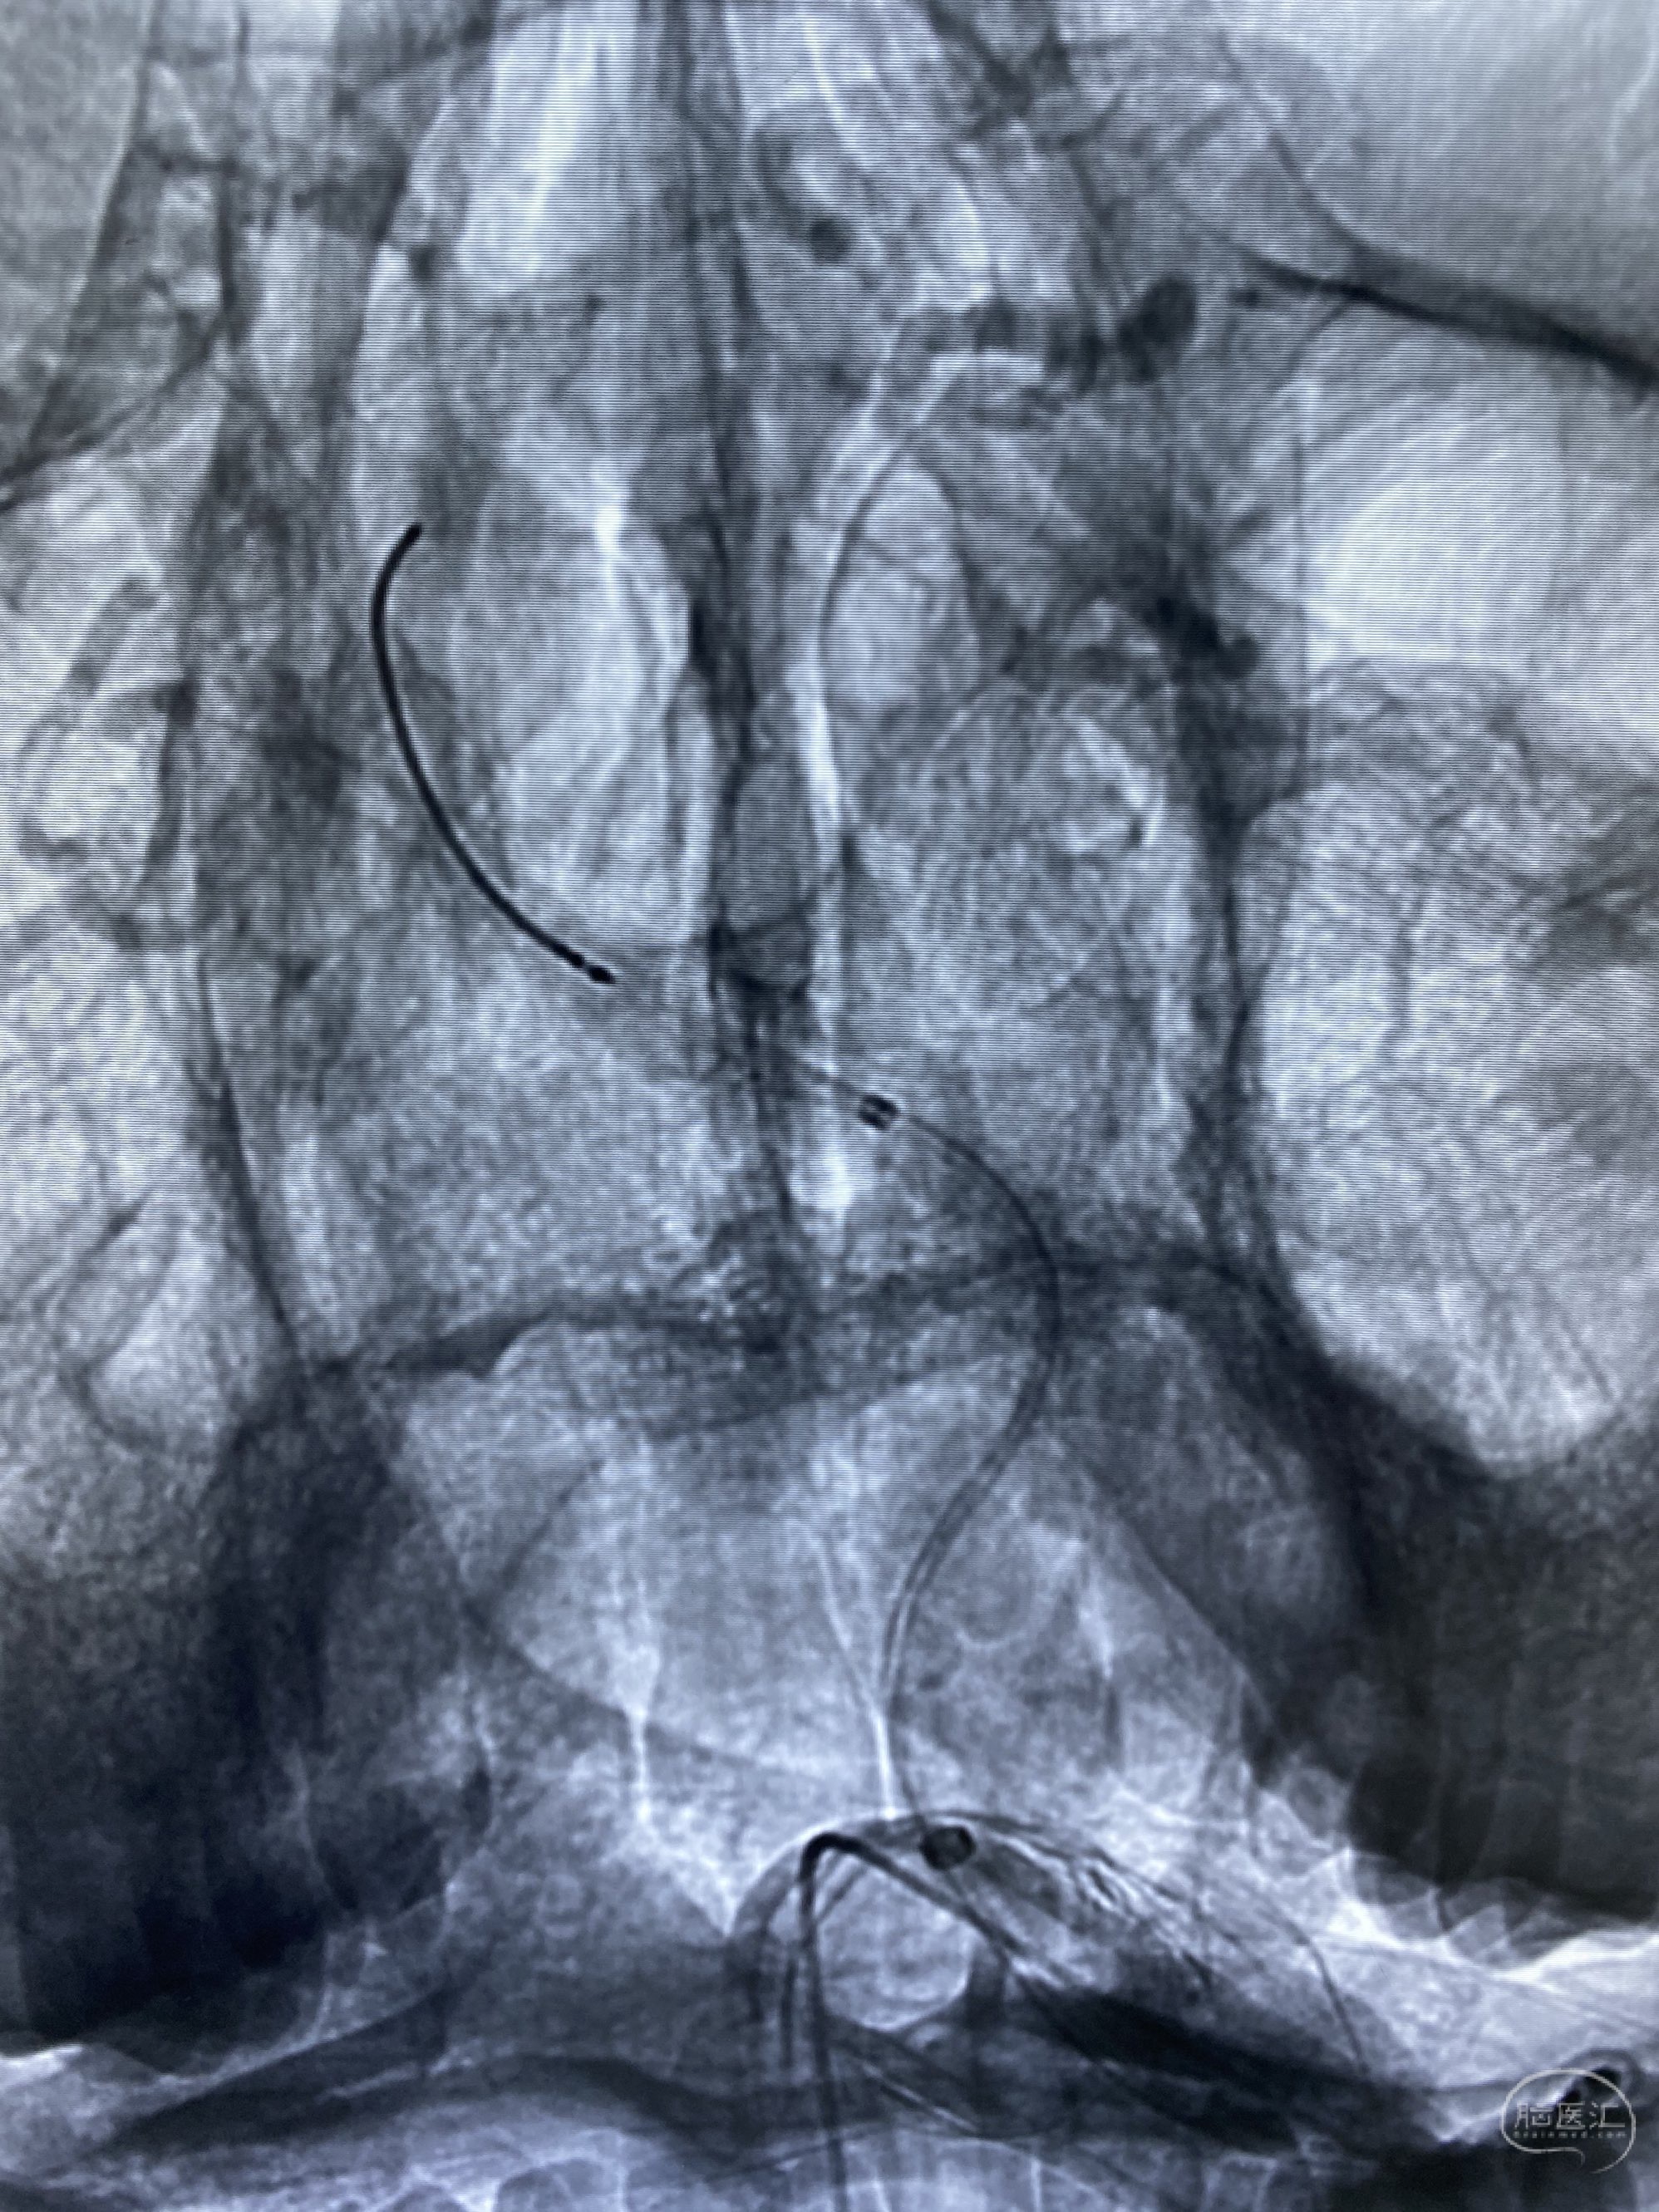

椎动脉颅内段多发夹层动脉瘤伴载瘤动脉狭窄pipeline flex植入

今日手术,TJG,M62Y,一期左侧颈动脉狭窄支架植入,二期椎动脉V4段多发夹层动脉瘤伴狭窄,常规支架辅助栓塞方法复杂又危险,血流导向装置植入快捷又安全。南阳市中心医院神经内科脑血管病介入团队pipeline flexFD植入两人导师资格。